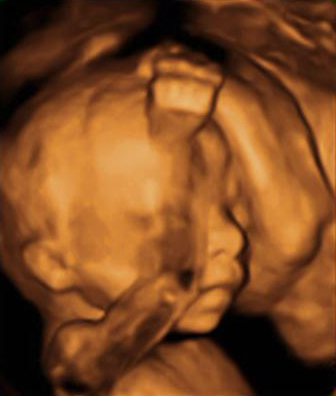

Desarrollo feto semana 21: Órganos internos casi listos

Ahora que tu bebé ha alcanzado la semana 21 de desarrollo fetal, está hecha una mujercita o un hombrecito: sus órganos internos están casi formados. Tanto es así, que dentro de muy pocas semanas, aunque naciera tendría posibilidades de nacer.

El bebé está hecho todo un gimnasta en la semana 21 de embarazo: da volteretas, estira brazos, usa las piernas para darse impulso, pedalea…, sobre todo cuando la madre está descansando. Todos estos movimientos le ayudan a la formación y desarrollo de su sistema muscular para cuando nazca.